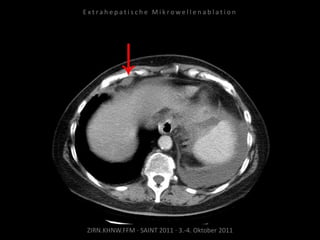

Bildgebung vor MWA:

CT 09.09.2010

ZIRN.KHNW.FFM · SAINT 2011 · 3.-4. Oktober 2011